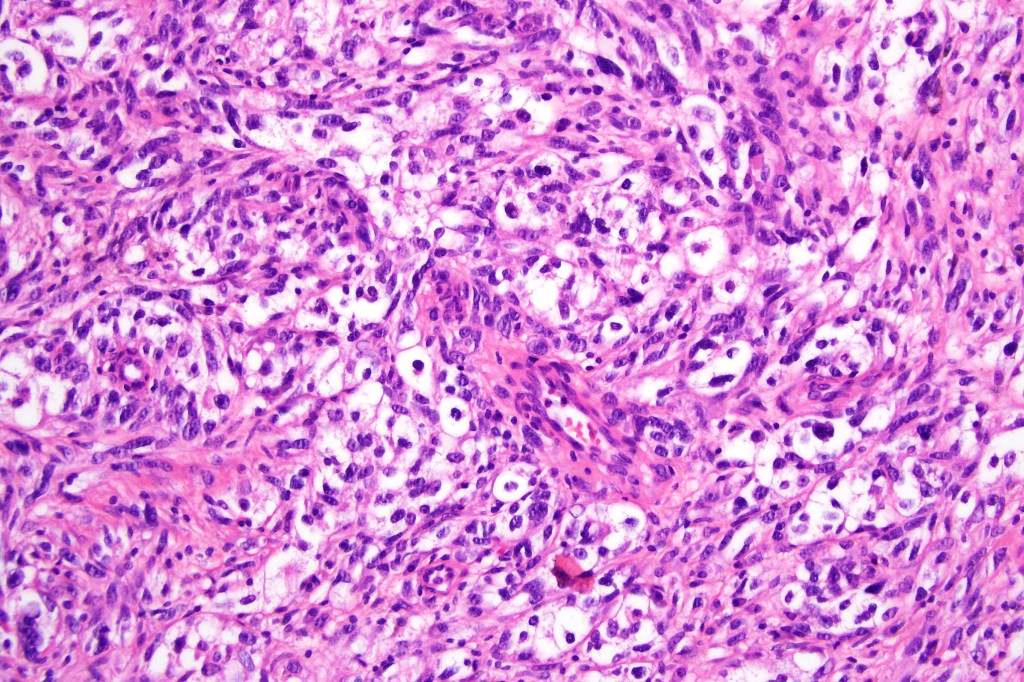

•Enlarged cells with copious eosinophilic, foamy or clear cytoplasm (some authors include melanoma with clear cell change in the same category)

•Variable pigmentation

•Nuclei vesicular or hyperchromatic

•Pleomorphism is not generally marked and indeed can be very subtle

•Variable mitotic activity